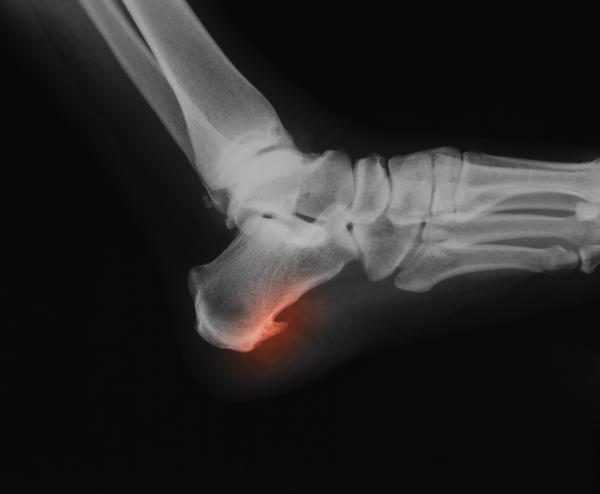

Um esporão calcâneo ocorre quando se gera uma formação óssea na zona inferior do osso do calcanhar, uma condição dolorosa e bastante incômoda que costuma ser resultado de uma fascite plantar não tratada. Devido a este quadro e aos incômodos que origina no paciente, a intervenção de um podólogo é fundamental para garantir uma adequada recuperação, um processo que pode ser longo. Curar ou tirar um esporão é trabalho de um podólogo, embora também existam alguns remédios naturais que o possam ajudar nisso. Enquanto não vai a um especialista, neste artigo do umCOMO explicamos-lhe como aliviar a dor de um esporão e melhorar seus movimentos.

A inflamação é a forma que o nosso corpo tem para proteger a zona sobrecarregada, o que se conhece como fascite plantar. Se esta condição não for cuidada e tratada, o corpo acabará por gerar uma calcificação na zona, ou seja, uma pequena formação óssea, o que causará dor e incômodos muito mais intensos e importantes, chegando inclusive a afetar a capacidade de caminhar distâncias médias e tendo impacto na realização de atividades cotidianas.

Se acha que se formou um esporão de calcanhar no seu pé, a primeira coisa que deverá fazer é consultar um médico ou especialista para o examinar e confirmar o diagnóstico.